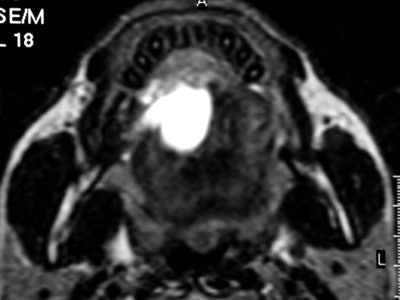

At today's session, Dr. Alexandra Borges, from the Portuguese Institute of Oncology in Lisbon, will present on the anatomy and imaging techniques relevant to pathologies of the oral cavity and salivary glands. She will provide useful tips regarding the choice and tailoring of imaging technique, and will review relevant anatomic relationships underlying the most common patterns of disease spread.

But to image this region of the body productively, radiologists need to be familiar with the intricate anatomy of the oral cavity, recognize the most common routes of disease spread, tailor imaging studies to specific clinical presentations, and issue meaningful reports answering pertinent clinical questions.

"Imaging may be the only way to assess clinically occult lesions such as the retromolar trigone in patients with trismus and the deep lobe of the parotid gland, therefore having a major impact on their management," she pointed out.

CT and MR are currently the primary imaging modalities to assess the oral cavity. CT is preferred in patients presenting with infectious/inflammatory syndrome. According to Borges, in patients presenting with oral cavity cancer, the use of dental CT software with the acquisition of para-axial and parasagittal high-resolution images in bone algorithm is most valuable in depicting early cortical bone erosion. MRI provides better soft-tissue resolution, and is the first choice in evaluating the deep extent of tumors and for the management of patients presenting with submucosal lesions.

In terms of technical issues to note when imaging the oral cavity, Borges has plenty of good advice. She points out that dental-related artifacts can be avoided by angling the axial sections parallel to the dental fillings on CT or opting for MRI. When lesions are located in the gingival sulcus, jugal or palatal mucosa, or the tongue, cheek puffing is very helpful to clearly depict the full extent of the lesion and separate the lesion from the adjacent mucosal surfaces, she noted.